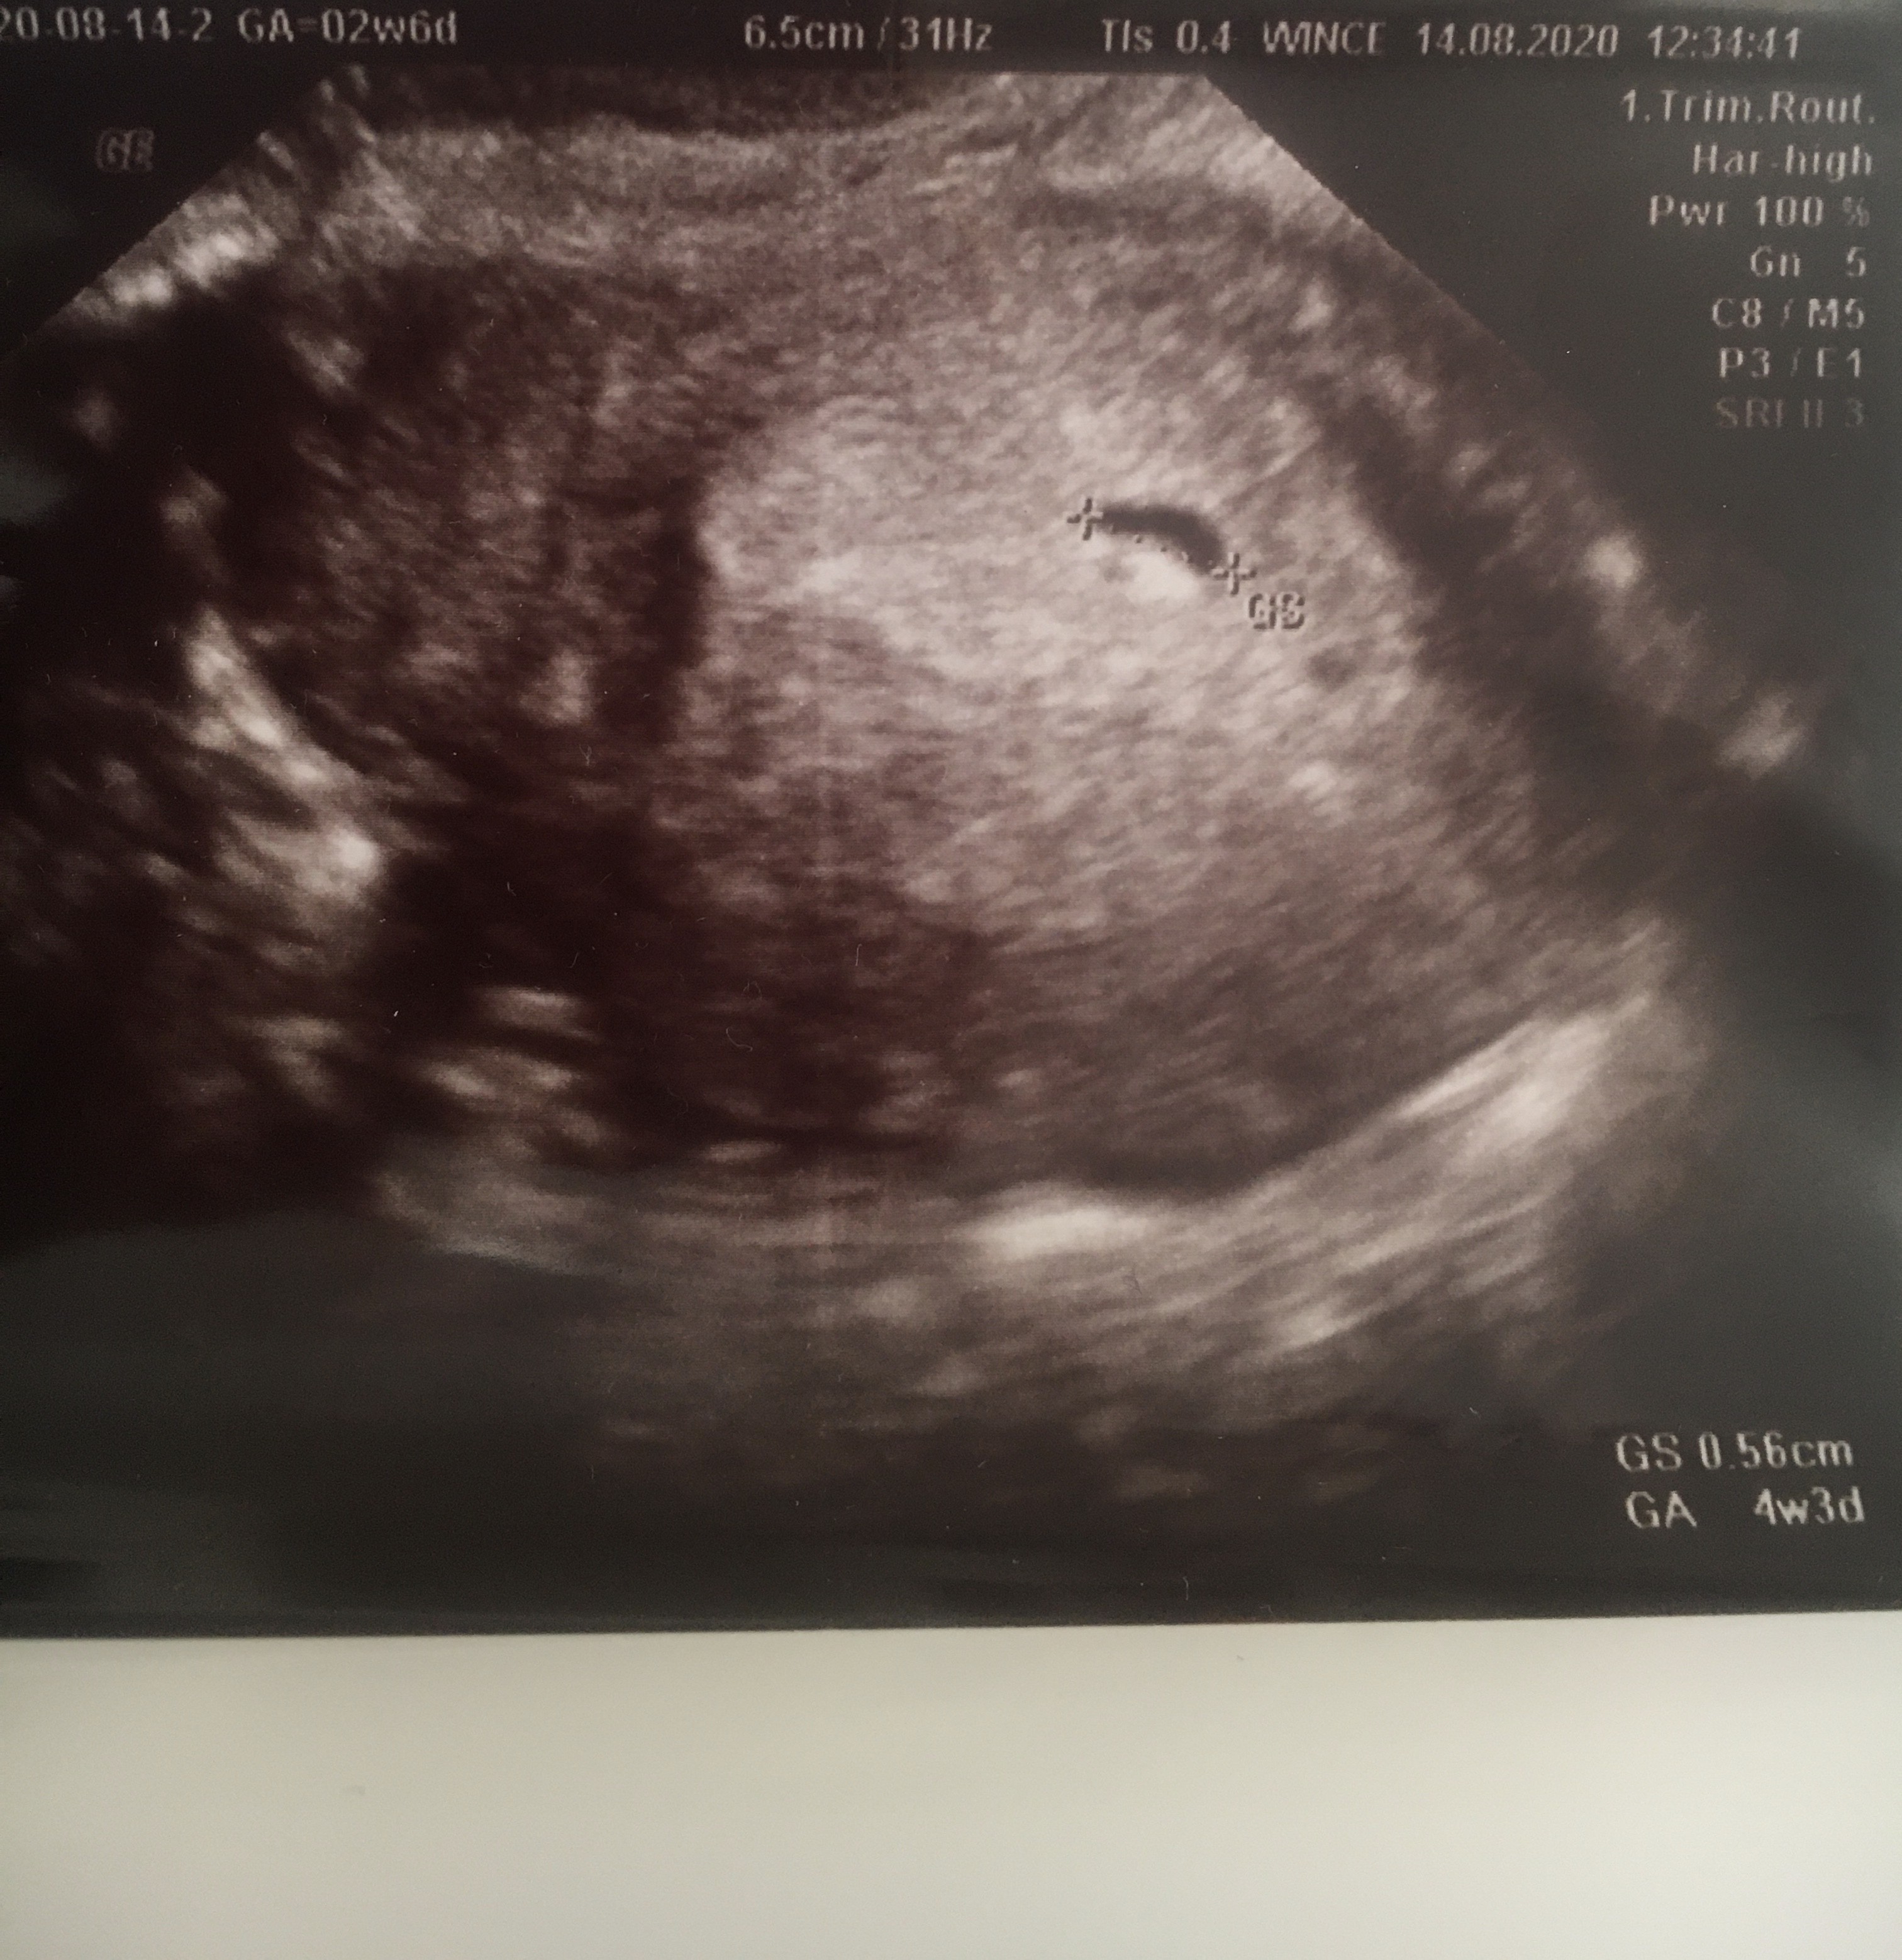

Tydzień temu w czwatek, 30.07 zrobilam test ciążowy-2 kreseczki. Ostatnia miesiączka 29.06 więc książkowo powinnam być aktualnie w 6 tygodniu ciąży. Od dnia spodziewanej miesiączki mocno boli mnie brzuch jak na okres stąd wczorajsza wizyta u Pani ginekolog która potwierdziła ciążę, jednak stwierdzila że jest ona malutka jak na swoj wiek bo pęcherzyk ciążowy ma wielkość 7.7mm .

Dziewczyny, pomocy. Czy coś z tego będzie? Ginekolog stwierdził że kształt pęcherzyka źle wróży bo jest spłaszczony. Jestem obecnie w 5 + 0 tyg. Na usg widoczny tylko sam pęcherzyk bez cialka żółtego i echa zarodka 😞

Załączniki

• C2EF38CD-4940-4F6A-95FE-F2BED745442E.jpeg

C2EF38CD-4940-4F6A-95FE-F2BED745442E.jpeg

1,4 MB · Wyświetleń: 224